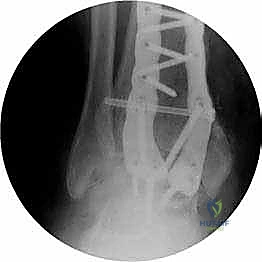

- الأشعة السينية أثناء الوقوف (Weight-bearing X-rays): هي الفحص الذهبي والأهم. يجب أن تؤخذ الأشعة والمريض واقف لتحمل الوزن. تظهر الأشعة تضيق المسافة المفصلية (دليل على فقدان الغضروف)، وجود نتوءات عظمية، تصلب العظم، وأي انحراف في محور المفصل.

| طرق العلاج | أدوية مضادة للالتهابات (NSAIDs)، أحذية طبية مخصصة (Rocker-bottom shoes)، دعامات الكاحل (AFO)، حقن الكورتيزون أو البلازما (PRP)، العلاج الطبيعي. | جراحة إزالة الغضاريف التالفة ودمج العظام (Arthrodesis) باستخدام مسامير وألواح معدنية. |

- تثبيت ميكانيكي حيوي أقوى: يتيح المدخل الأمامي وضع شريحة معدنية (Anterior Plate) على الجانب الأمامي للمفصل. من الناحية الميكانيكية الحيوية (Biomechanics)، يعتبر الجانب الأمامي هو "جانب الشد" (Tension side) أثناء المشي. وضع الشريحة هنا يوفر تثبيتاً فائق القوة ويقلل من معدلات عدم الالتئام.

- التخطيط الجراحي الرقمي: باستخدام صور الأشعة المقطعية، يقوم الدكتور هطيف بتخطيط الجراحة على الكمبيوتر لاختيار حجم المسامير والشرائح المناسبة بدقة مليمترية.